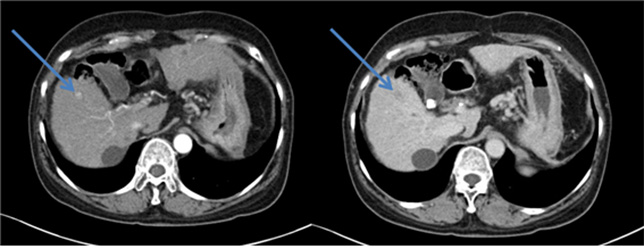

- 세균, 원충, 진균등의 원인균이 간실질내로 침투하여 증식함으로써 간실질내 종괴 양상의 고름을 형성하는 질환입니다.

- 국내에서는 과거 위생상태가 좋지 못했을 때는 아메바성 간농양이 흔했으나, 최근에는 위험요인을 가진 환자에서 화농성 간농양이 증가하고 있습니다.

- 임상양상 ; 증상은 다양합니다. 발열, 복통, 압통등이 있으며, 비특이적 증상으로 오한, 식욕부진, 체중감소, 오심, 구토, 전신쇠약, 무력감이 있습니다.

- 진단 ; 과거에는 불명열의 원인이었으나, 최근에는 영상기술의 발전으로 진단할 수 있습니다. 간초음파, 간복부전산화단층촬영등의 방법으로 진단이 가능합니다.

- 치료 ; 적절한 배농과 항생제로 치료가 가능합니다. 하지만 크기가 크거나 외과적 질환이 동반된 경우 수술을 고려할 수 있습니다.